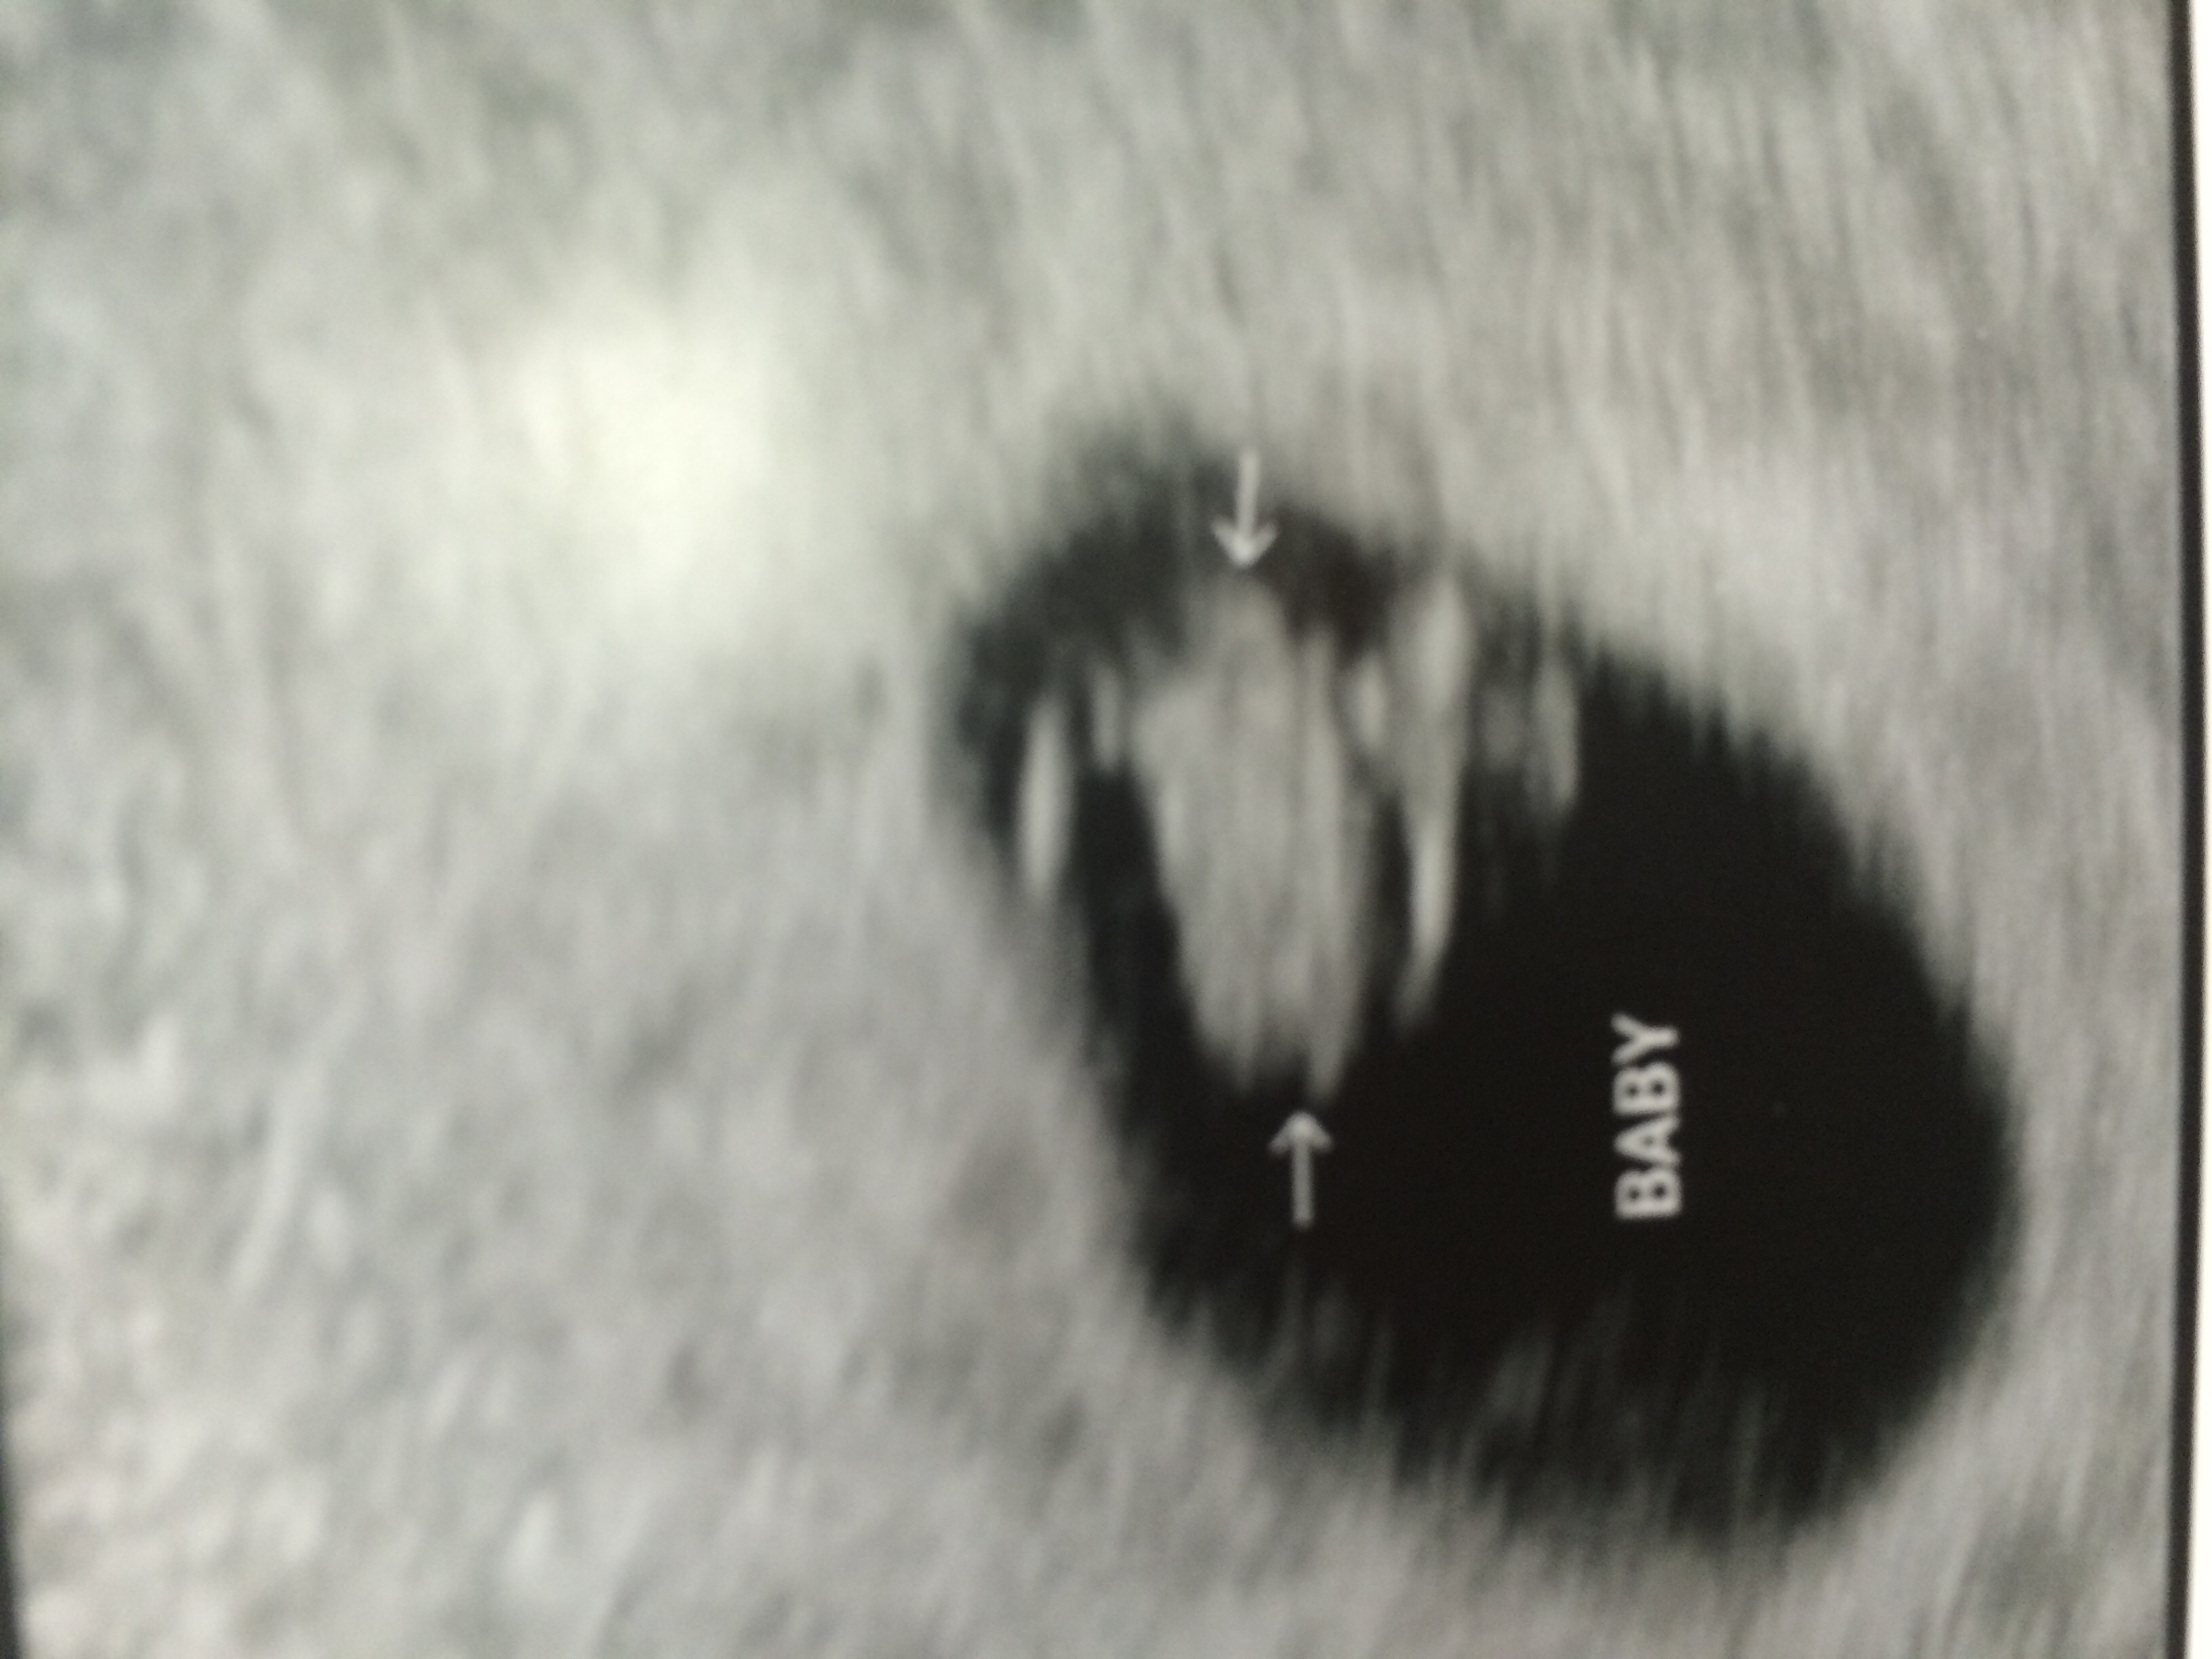

Our little one today! 6w1d

108HB